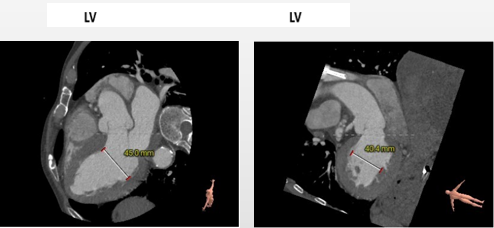

冠脉高度可,未见冗长瓣叶,左室内偏径大,横位心(71°)

• 主动脉瓣环与水平面夹角71度,横位心,主动脉弓角度较小,弓距长度可。